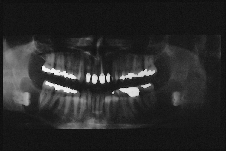

M = male A 42-year-old Caucasian man was referred to the department of dentistry of the Sunnybrook Health Science Centre by an outside emergency dental service for the evaluation of an asymptomatic, cystic lesion in the right mandible. Intraoral examination revealed an extensively restored dentition and clinically absent third molar teeth. No extraoral swellings or tenderness in relation to the mandibular third molars was noted. The patient's medical history was nonsignificant except for a case of bronchitis and chronic fatigue. There were no associated syndromes present. A panoramic radiograph showed absent upper third molars. Bilateral, unilocular well-defined corticated radiolucencies surrounding both unerupted mandibular molars were identified. The anterior border of both radiolucencies appeared to involve the distal root of the second molar (Fig. 1). Both third molars were grossly displaced to the inferior border of the mandible.